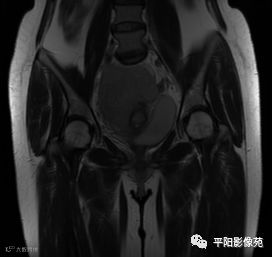

MRI表现

T2冠状位

(宫腔内见金属节育环伪影)宫颈区见不规则形等T1稍长T2信号软组织肿块,DWI序列呈明显高信号,大小约为3.87cmX2.64cm,双侧宫颈基质低信号环连续性中断,病灶向子宫右后上方生长,周围脂肪间隙模糊,增强扫描明显强化,强化程度低于子宫及宫颈实质;子宫后方、子宫直肠间隙见不规则形长T1长T2信号软组织肿块,DWI序列呈高信号,大小约10.12cmX4.82cmX10.29cm,病灶呈分叶状,向下方生长与宫颈分界不清,与直肠分界尚清,增强扫描明显不均匀强化。